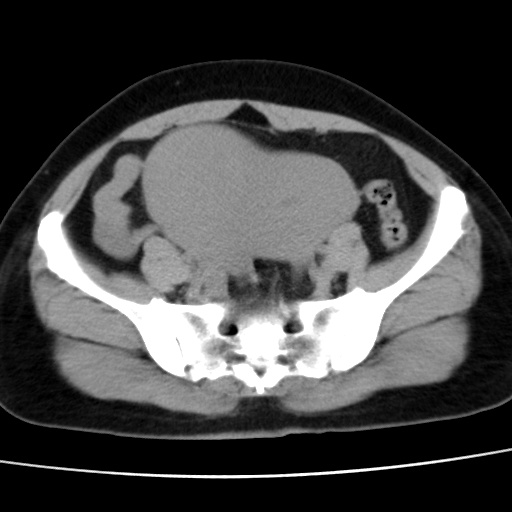

子宫多发肌瘤吗

多发性子宫肌瘤.

考虑多发子宫肌瘤,子宫直肠窝双囊性占位,另直肠周围脂肪密度增高,不知有何病史

支持考虑多发子宫肌瘤~!子宫直肠陷凹积液?

支持考虑多发子宫肌瘤~!子宫直肠陷凹积液!

子宫肌瘤,宫体部后方见液性密度影,是肠道还是子宫与直肠陷窝积液不好说,我觉得它的位置有点高

患者发热,而子宫直肠窝液性灶有明显边缘且局限且囊性,不除外为包裹性积液或脓肿

1)考虑子宫肌瘤可能性大。2)子宫后方囊性占位性病变,不排除卵巢囊肿可能。

考虑多发子宫肌瘤。子宫后方囊性占位性病变,不排除卵巢囊肿可能。